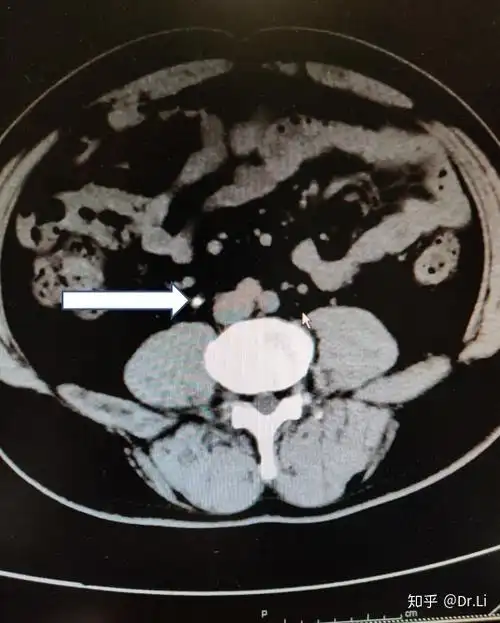

箭头所指为输尿管结石箭头所指为输尿管结石ct检查是发现结石最有效的